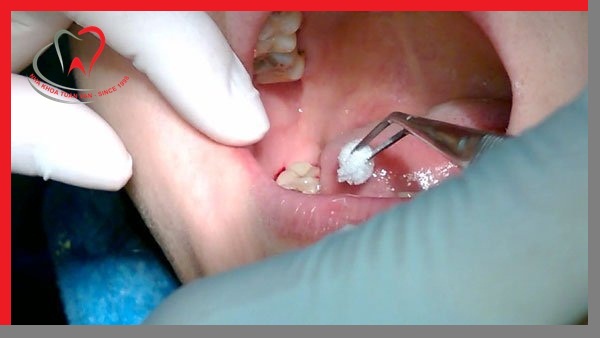

Bước 4: Tiến hành nhổ răng

Bác sĩ sẽ tiến hành rạch nướu để dễ dàng thực hiện nhổ răng, những trường hợp răng mọc ngầm bắt buộc phải rạch nướu.

Sử dụng các bộ dụng cụ riêng đã được vô trùng, vô khuẩn để tiến hành nhổ răng. Nhiều nha khoa hiện nay đang sử dụng phương pháp nhổ răng bằng sóng siêu âm diễn ra nhanh chóng, không đau.

Sau khi răng đã được nhổ ra khỏi khung hàm sẽ tiến hành khâu vá nướu hoặc tiến hành bước tiếp theo trong quá trình phục hình (trồng Implant là phương pháp tốt nhất hiện nay).